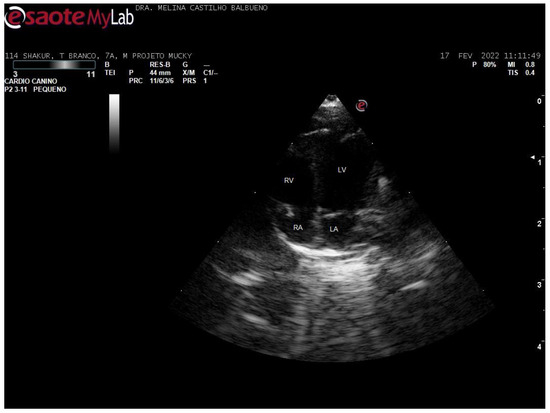

- Balbueno, M.C.S.; Martins, J.A.; Malaga, S.K.; Forato, J.; Coelho, C.P. Dilated cardiomyopathy phenotype in Callithrix penicillata (E. Geoffroy, 1812): Case report. J. Med. Primatol. 2024, 53, e12678. [Google Scholar]

de Souza Balbueno, M.C.; Martins, J.A.; Malaga, S.K.; Vanstreels, R.E.T.; de Paula Coelho, C. Echocardiographic Parameters of Callithrix spp. Under Human Care. Animals 2025, 15, 1875. https://doi.org/10.3390/ani15131875